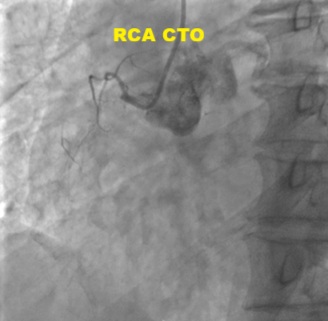

Coronary angiogram revealed mild LAD stent ISR, RCA CTO and severe obtuse marginal (OM) branches disease. PCI of the OM branches with drug-coated balloons was performed. Subsequently electively admitted for stage PCI to RCA CTO.

Dual access via right radial and femoral arteries. Failed to cross antegradely the proximal cap CTO using UltimateBros3 and Fielder XT-R guidewires / Corsair Pro, and retrogradely via septals collateral. Initially decided to abandon the procedure as deem small RCA vessel size. Unfortunately noted coronary perforation at proximal RCA CTO site, temporary tamponade with microcatheter. Retrograde Suoh3 wire via LAD epicardial collateral successfully crossed the distal cap of proximal RCA CTO, however, Caravel microcatheter unable to pass through the distal RCA branch for better support. Gladius EX14 guidewire supported with Corsair Pro microcatheter swiftly crossed the proximal cap antegradely (using the Suoh3 as the guide from retrograde) successfully till distal RCA branch. Caravel and Suoh3 removed retrogradely without complication. Predilate the RCA (prolonged balloon inflation) using SC 2.0x15mm (6-8atm, 3mins each) - to facilitate the plaque sealing of the perforation site. IVUS performed confirmed the wire in the true lumen. Stented with 2 overlapping DES 2.25x33mm (nominal) and 3.0x33mm (nominal). Noted the stent was from RCA-acute marginal branch, distal RCA was smaller vessel. Post-dilated distal stent with NC 2.5x15mm (nominal) while proximal stent with NC 3.0mm and NC 4.0mm. IVUS performed good stent apposition/expansion, with satisfactory MSA. Good angiographic result, TIMI 3 flow, no dissection/perforation noted. No pericardial effusion from echocardiography.